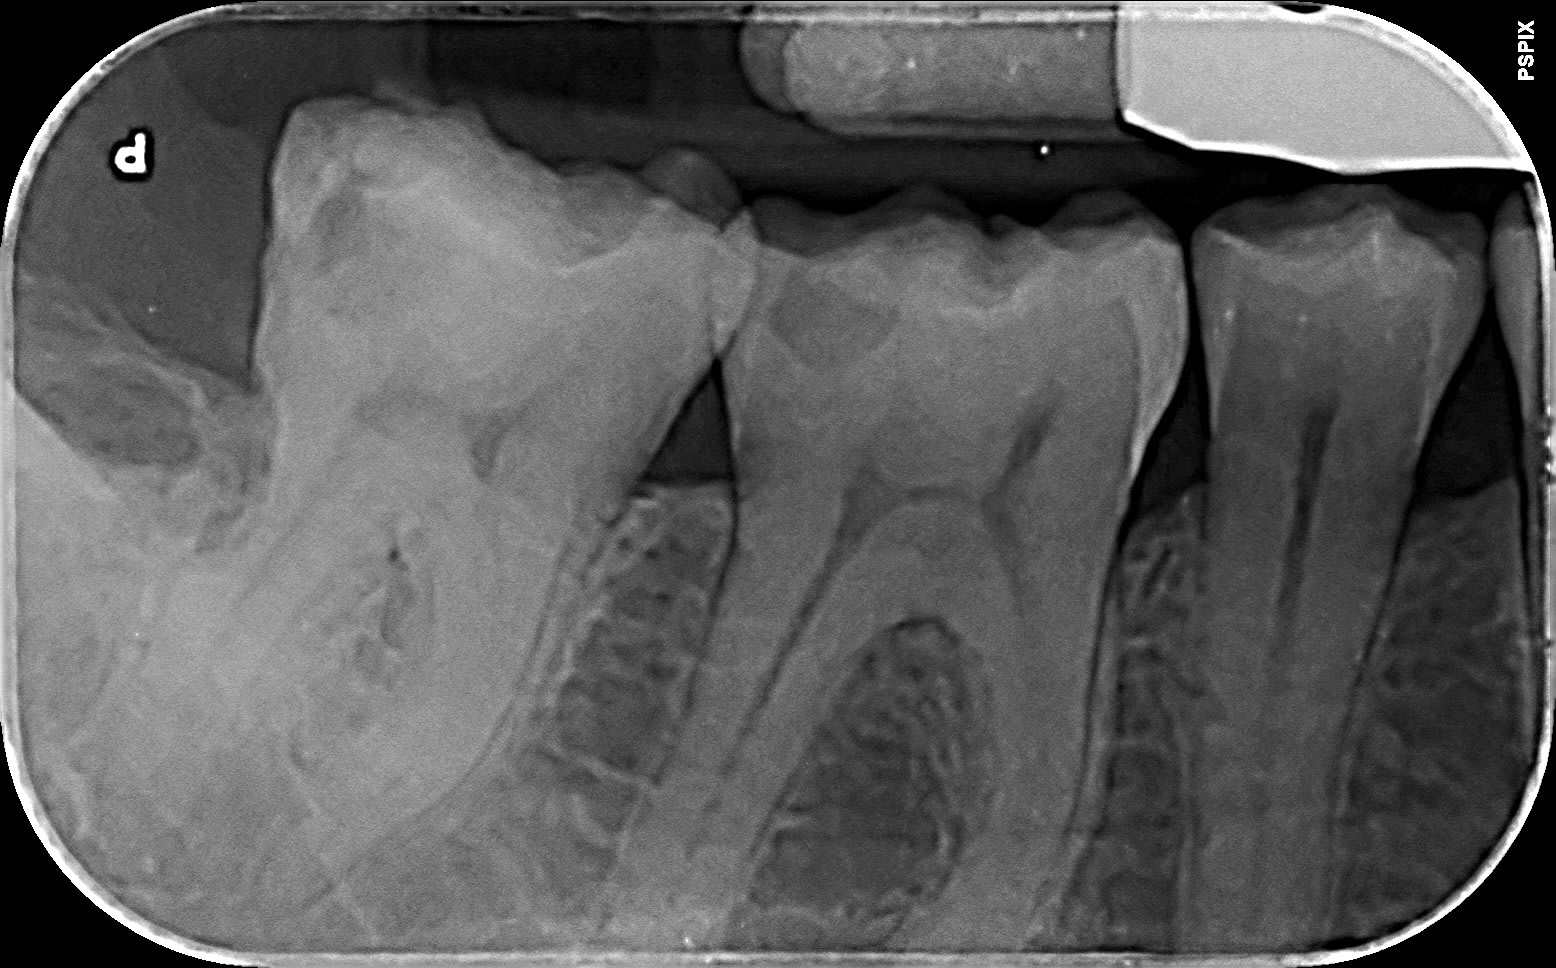

37 carie DV juxta pulpaire, mais pas que... vous feriez quoi?

Roc 26620 37 qahwrz - Eugenol

L'image radiculaire sur la distale, c'est un souvenir de la 8?

Si on parle de la carie coronaire, sans symptômes, tu peux tout faire, coiffage, onlay, couronne, tant que tu ne crées pas une poche en distal.